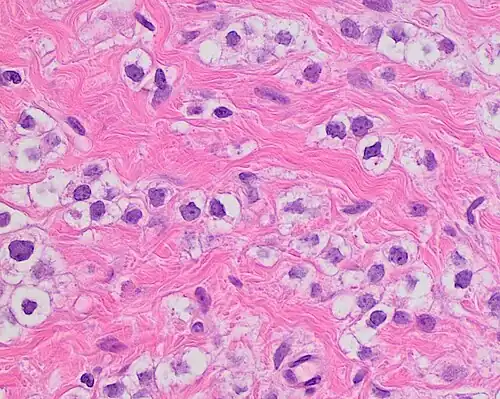

Nuclear pleomorphism

This parameter assesses whether the cell nuclei are uniform like those in normal breast duct epithelial cells, or whether they are larger, darker, or irregular (pleomorphic). In cancer, the mechanisms that control genes and chromosomes in the nucleus break down, and irregular nuclei and pleomorphic changes are signs of abnormal cell reproduction.

Note: The cancer areas having cells with the greatest cellular abnormalities should be evaluated.

- 3 points: nuclei with marked variation in size and shape

Invasive ductal carcinoma with marked nuclear pleomorphism.